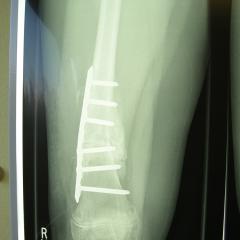

XRays